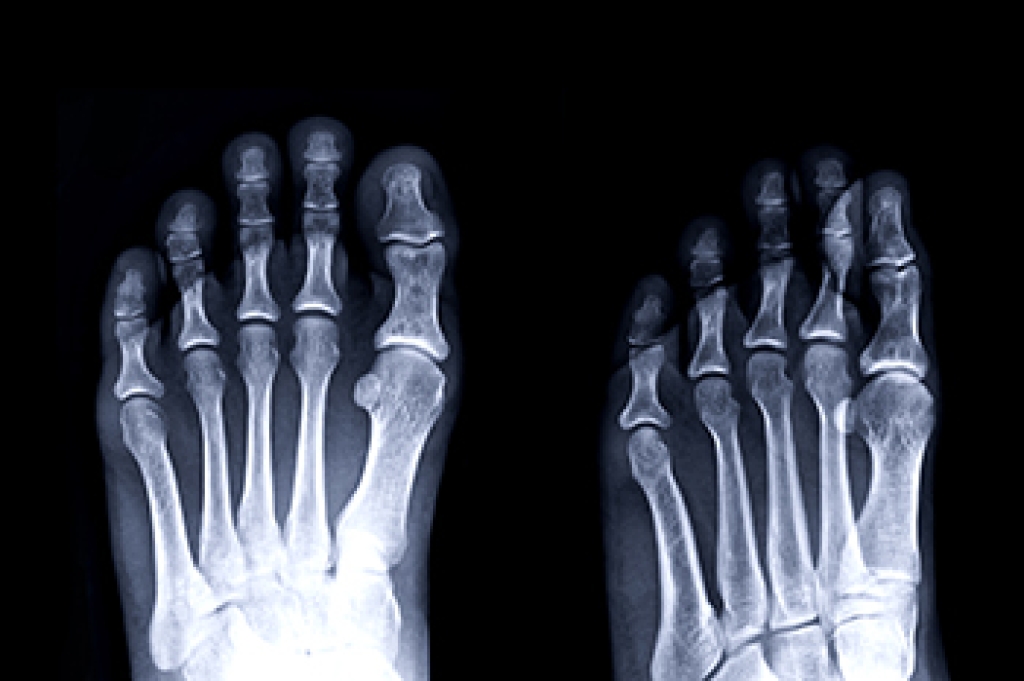

Diagnosis

Due to the wide variety of potential causes of ankle pain, podiatrists will utilize a number of different methods to properly diagnose ankle pain. This can include asking for personal and family medical histories and of any recent injuries. Further diagnosis may include sensation tests, a physical examination, and potentially x-rays or other imaging tests.